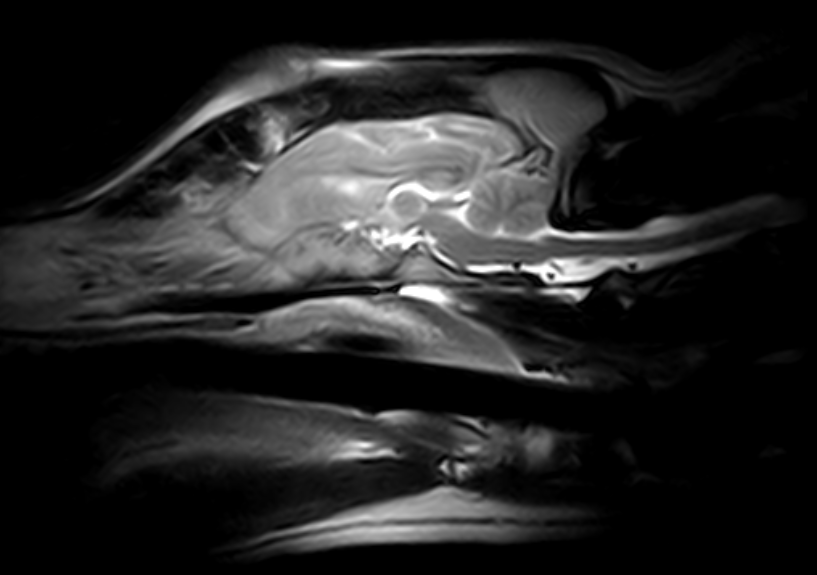

IMÁGENES CLÍNICAS

En la sección de imágenes clínicas, destacamos la precisión y claridad de nuestros estudios, respaldados por un equipo de radiólogos especializados en medicina veterinaria. Nos enorgullece ser un aliado confiable para veterinarios y clínicas, brindando un servicio rápido y eficiente para ayudar en la toma de decisiones clínicas fundamentadas.